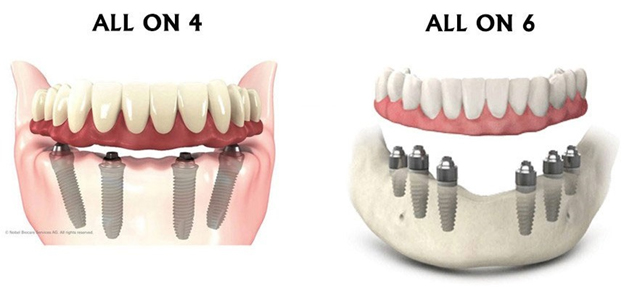

What Is Better Is It All on Four or All on Six Dental Implants? Earlier, removable dentures were the only…